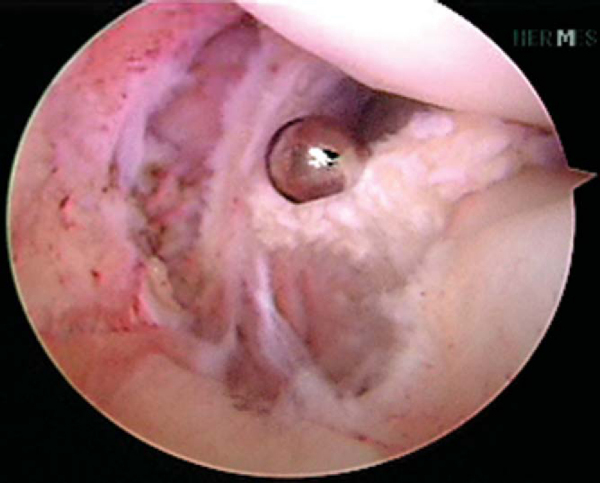

The tibial tunnel of the PCL reconstruction is addressed first. A 70-degree arthroscope is placed through the anterolateral portal and used to visualize the PCL tibial footprint. A spinal needle is used for establishment of the posteromedial portal. A transseptal portal is established as described by Ahn et al. [1] [2] The PCL footprint is exposed by débridement of the surrounding synovial tissue with a PCL curet and arthroscopic shaver (

Fig. 71-4

). Care is taken to avoid injury to the neurovascular bundle posteriorly. The 30- and 70-degree arthroscopes are frequently exchanged in the posteromedial and anterolateral portals, respectively, for adequate visualization. A PCL drill guide is set to 50 to 55 degrees, and its placement posteriorly is confirmed with fluoroscopy and arthroscopy. A vertical incision is made over the anteromedial aspect of the proximal tibia (or the anterolateral aspect if an ACL reconstruction is not required and a lateral incision will be performed).